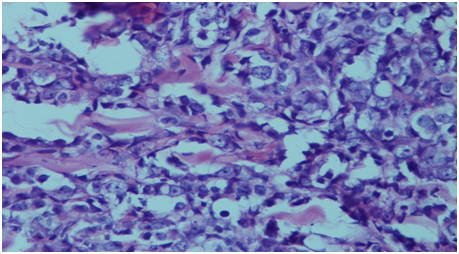

Figure 2 Histopathology of the skin nodule showing infiltration by prostatic adenocarcinoma.

Prostatic carcinoma is common cancer in elderly men. It mostly metastasis to bone, lung, liver, adrenal and lymph nodes. Metastasis to skin is rare and accounts for less than 1% of cutaneous metastases,2 with less than 80 cases published in the literature.4,5 Clinically, patients present as asymptomatic papule, nodule or occasionally sclerodermoid lesion over suprapubic region, lower abdominal area, inner aspect of thigh and genitalia.6 Rare site of cutaneous metastasis include chest, scalp and face.1 The probable route of spread are dissemination vialymphatics and spread through perineural lymphatics.6,7 The cutaneous metastasis may resemble angiosarcoma, cellulitis, mammary Paget’s disease, sebaceous cyst, Sister Joseph nodule, basal cell carcinoma, pyoderma, morphea, and trichoepithelioma.6 The definite diagnosis is done by skin biopsy. The tumour cells show positivity for PSA and cytokeratin. The serum PSA levels are also markedly elevated in these cases. The cutaneous metastasis represents advanced stage of the disease and associated with poor prognosis. Most of the patients die within six months of diagnosis.3 The treatment at this stage is palliative care which includes keeping the lesion dry and clean (Figure 1 & Figure 2).

We report a 55 year old male who presented with multiple papulonodular lesions in suprapubic region, inner aspect of both thighs & in the scrotum. The nodules were 0.3-1.5 cm in size. On local examination the nodules were fleshly in color, firm, smooth surfaced & subcutaneous in location and free from deep tissue. FNAC from the nodules showed adenocarcinoma. Then a search for the primary site was made which on clinical examination patient had history of thin stream, decreased flow, dysuria, hesitancy, nocturia & loss of appetite but had no h/o hematuria. On DRE prostate was found to be enlarged, hard, nodular & fixed to rectal wall mucosa. Serum PSA level of the patient was 45.4ng/ml. TRUS guided biopsy of prostate and biopsy of skin nodule was done. HPE of prostate revealed high grade adenocarcinoma (gleason score 3+4). Biopsy of skin nodule showed infiltration by the tumor cells. Bone scan was negative. CT scan of the patient was not done.